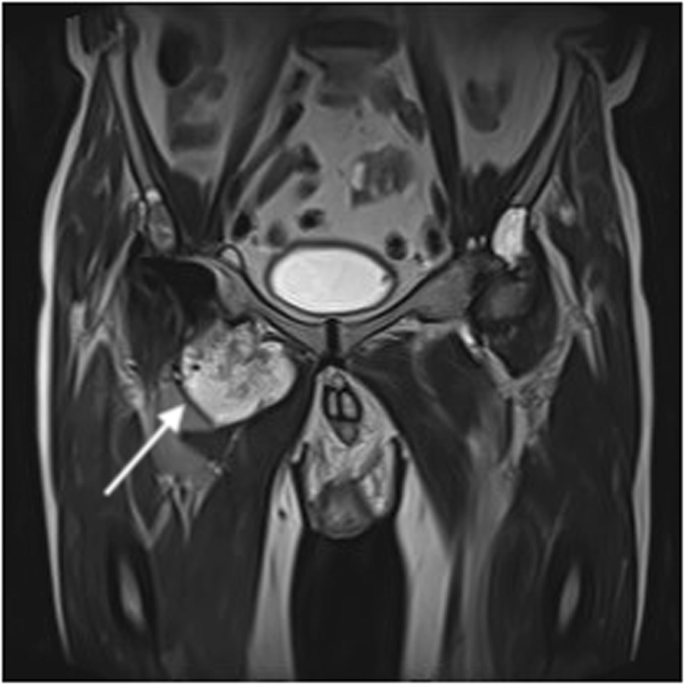

In view of the intermittently discharging sinus, the clinical diagnosis at initial orthopaedic assessment was PJI. Computed tomography of the pelvis showed a large collection around the right hip extending into the adductor compartment. The urinary tract appeared normal and there was no evidence that the collection was associated with any part of it. Magnetic resonance imaging (MRI) of the hip demonstrated a large, lobulated soft tissue mass arising in relation to the hip joint and prosthesis, which was felt to be consistent with a diagnosis of metallosis and pseudotumour due to aseptic lymphocyte-dominated vasculitis-associated lesions (Fig. 1) [3].